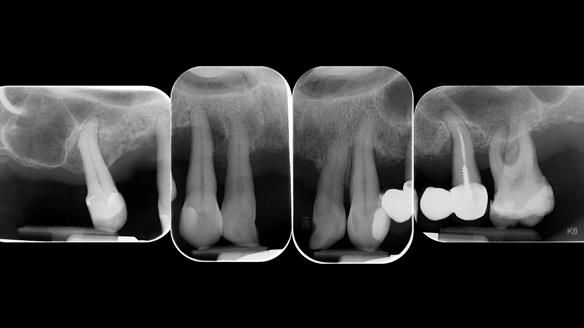

She had previously suffered from generalised periodontitis – stage IV, grade C, currently stable, with reduced attachment across the upper arch.

By the time she came to me, her periodontal condition was stable — but the aesthetics in the upper jaw were very poor.

Dr Syed Abad — my colleague and a Specialist in Periodontics — had successfully stabilised her gum health.

- Her upper jaw had insufficient bone and would have required significant augmentation.